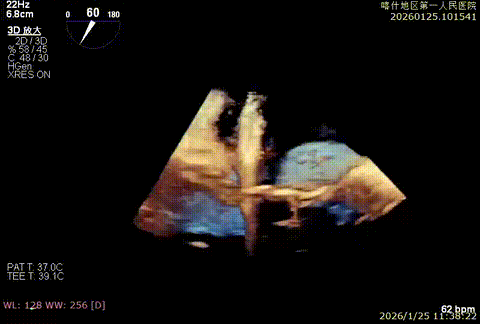

该例患者为VFMR,术前制定手术策略:患者二尖瓣重度反流,后叶严重栓系,心房心室扩大。患者瓣口面积4.5cm2,预计使用两枚XTR解决患者瓣叶脱垂和反流。考虑到先于2区进行钳夹,应该能获得足够的房间隔穿刺高度。术中经不断调整穿刺位点,最终穿刺高度4.4cm。成功穿刺后将第一枚XTR送入二尖瓣正上方,进行弹道测试Orientation调整后,最终定位于2区正上方下左心室。第一枚夹子在左室成功捕捞和钳夹瓣叶后,瓣叶反流程度显著降低,夹子外侧仍见部分反流,随后在第一枚夹子外侧再次放置一枚XTR,瓣叶反流程度进一步降低至微量。通过TEE观察,二尖瓣双孔组织桥稳定,跨瓣压差3mmHg,肺静脉逆流改善明显,手术安全结束。

X-plan重度反流

3D enface后叶栓系

3D enface观察反流

术后压差3mmHg